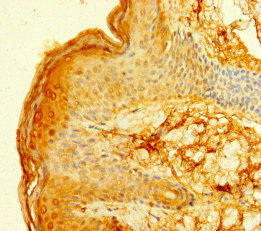

Immunohistochemistry of paraffin-embedded human skin tissue using CSB-PA008532LA01HU at dilution of 1:100